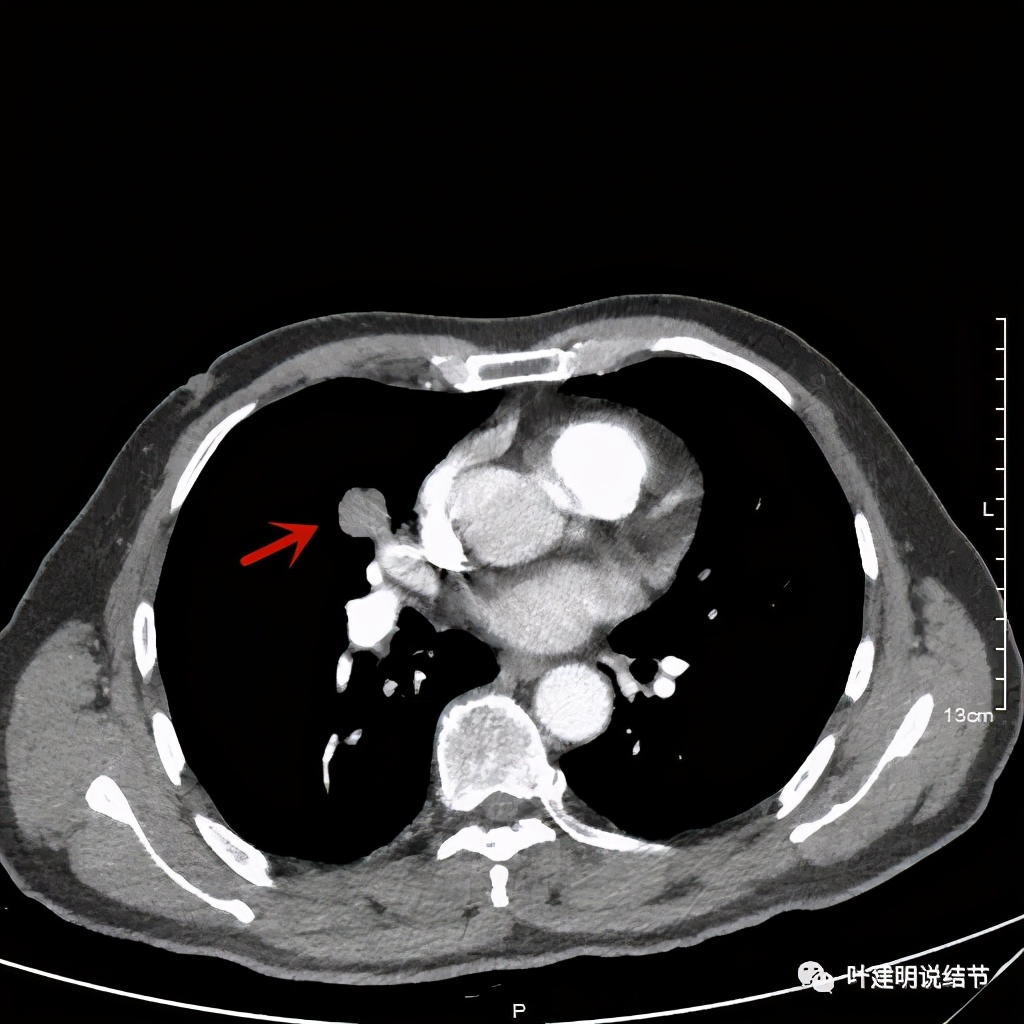

纵隔窗分叶明显,密度不均

黄色箭头示病灶附近淋巴结或癌结节可能性大